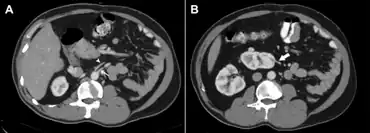

Ectopic kidney describes a kidney that is not located in its usual position. It results from the kidney failing to ascend from its origin in the true pelvis or from a superiorly ascended kidney located in the thorax.[1]